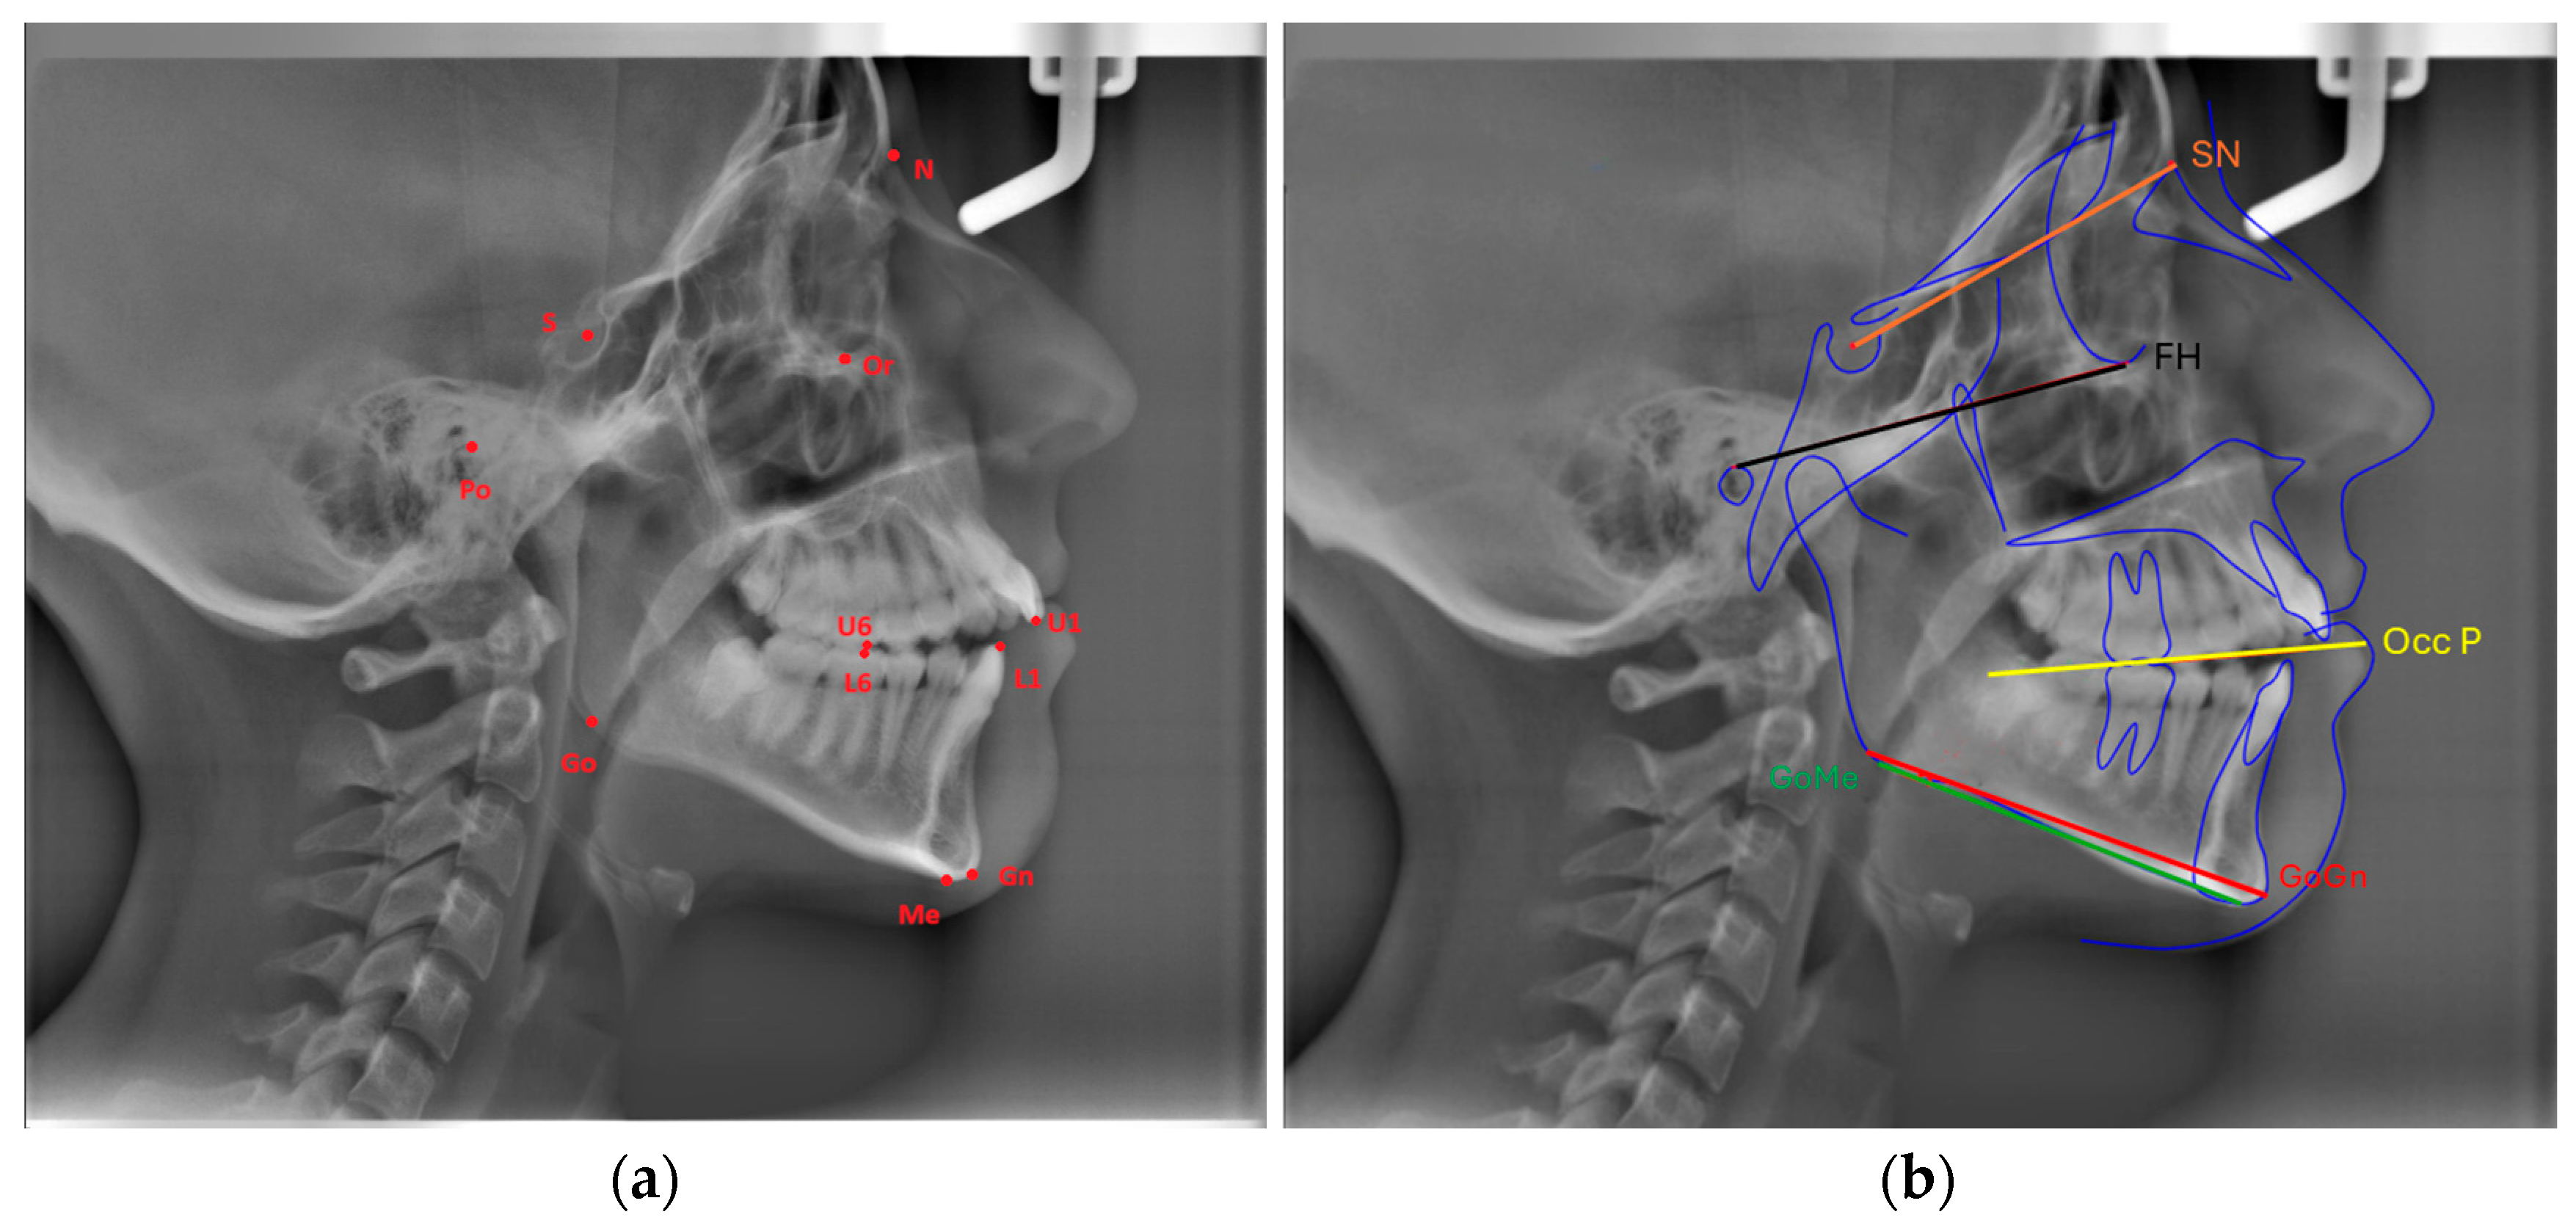

Eleven landmarks were marked on each cephalogram (Or, Po, Go, Gn, Me, S, N, U6, U1, L6, L1), and the following three measurements were made using three planes formed by these landmarks (Figure 1a,b):

FMA: The angle formed between the Frankfort Horizontal Plane (Or-Po) and the mandibular plane (Go-Me).

SN-GoGn (Mandibular plane angle): The angle between the GoGn and SN lines.

Cant of Occlusal Plane: The angle between the occlusal plane (the line bisecting the overlapping cusps of first molars and incisor overbite) and the Frankfort Horizontal Plane.

Figure 1. (a) Cephalometric landmarks and their definitions: Or (Orbitale): The most inferior point of the orbital floor, Po (Porion): Superior point of the meatus acusticus exter-nus, Go (Gonion): Posteroinferior point of the angulus mandibula formed by the intersection of posterior border of the mandibular ramus and the inferior border of the mandibular corpus, Gn (Gnathion): The most anteroinferior point of the mandibular symphysis between pogonion and menton, Me (Menton): The most inferior point on the mandibular symphysis, S (Sella): The center point of the sella turcica, N (Nasion): The most anterior point on the nasofrontal suture, U6: Tip of the mesiobuccal cusp of upper permanent first molar, U1: Incisal tip of the maxillary central incisor, L6: Tip of the mesiobuccal cusp of lower permanent first molar, L1: Incisal tip of the mandibular central incisor. (b) cephalometric measurements.